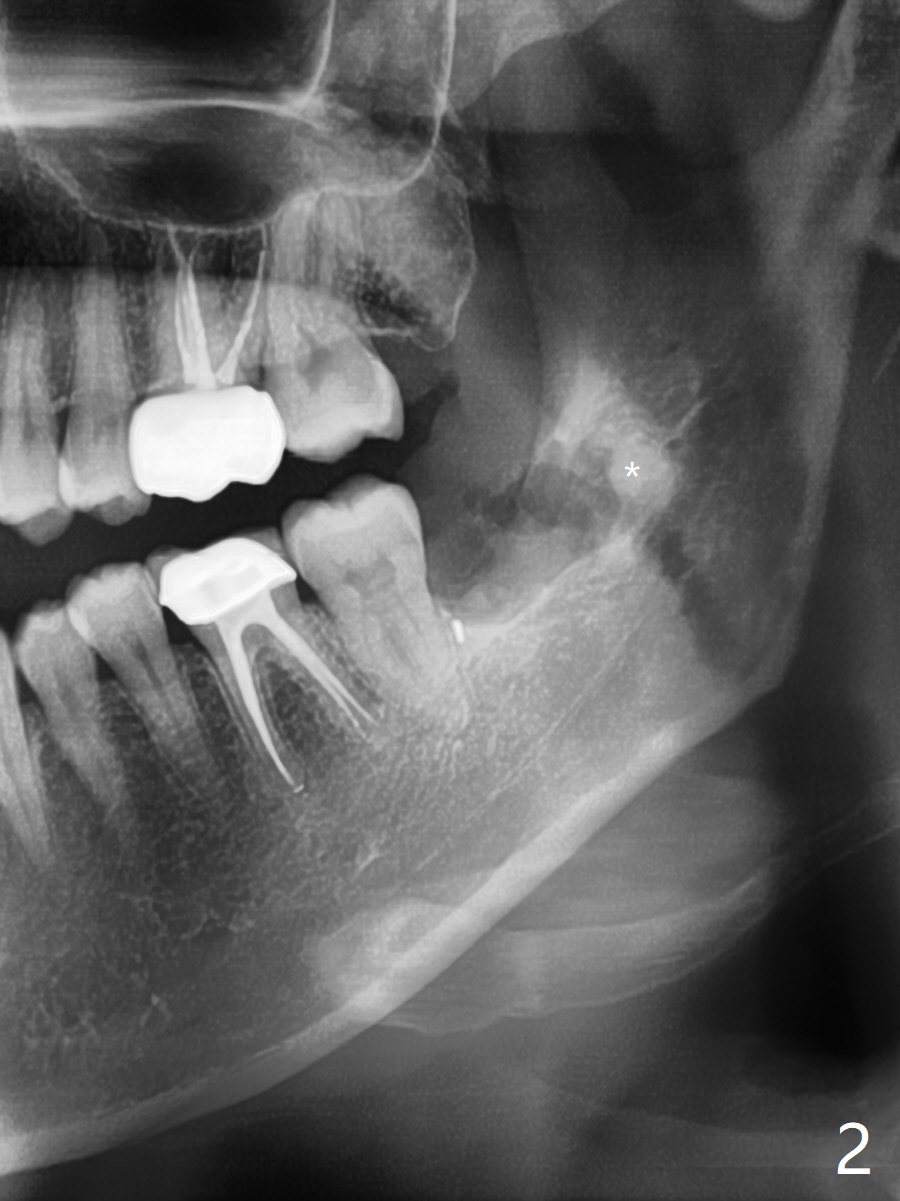

A 41-year-old woman (dental phobic) requests extraction of the tooth #17 because of food impaction (Fig.1). The fractured root tip (Fig.2 *) is so deep that the longest surgical length fissure bur can not reach in spite of multiple sectioning. The nervous patient agrees not to remove the root tip because of pain associated with root tip loosening. The fractured bur tip cannot be found clinically. CBCT should have taken for bur location and the proximity of the root tip to the Inferior Alveolar Canal. To prevent dry socket, Osteogen Plug is placed in the radicular portion of the socket (Fig.3 O), while allograft (A) in the coronal part of the socket. With Collagen Plug placed superficial to the allograft, 4-0 plain gut suture is used to close the socket. The patient returns 11 days postop with chief complaint of "pain returns for 2 days, affecting sleep. Small particles came out". #17 gingiva is healthy, although there is tenderness on deep palpation of #17 D. There is no exudate. Chlorhexidine irrigation is done with 2 syringes with pain relief. Augmentin is prescribed for 7 days. Pain disappears in ~ 1 month. Bone fills the socket 1 year postop (Fig.4).